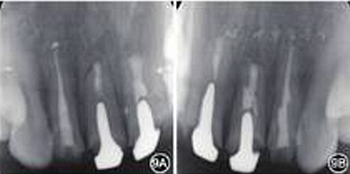

圖9 6個月復(fù)查患者根尖X線片 A:根尖病變愈合;B:根尖病變接近愈合